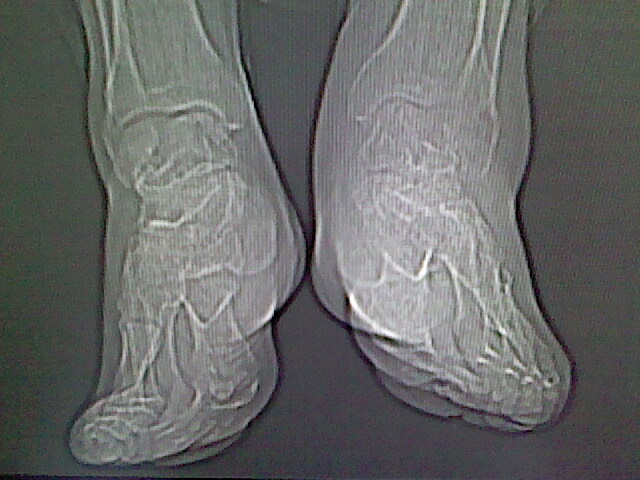

标题: CT16814:男,76岁,左小腿疼痛,不能站立 大家给看看 [打印本页]

男,76岁,左小腿疼痛,不能站立